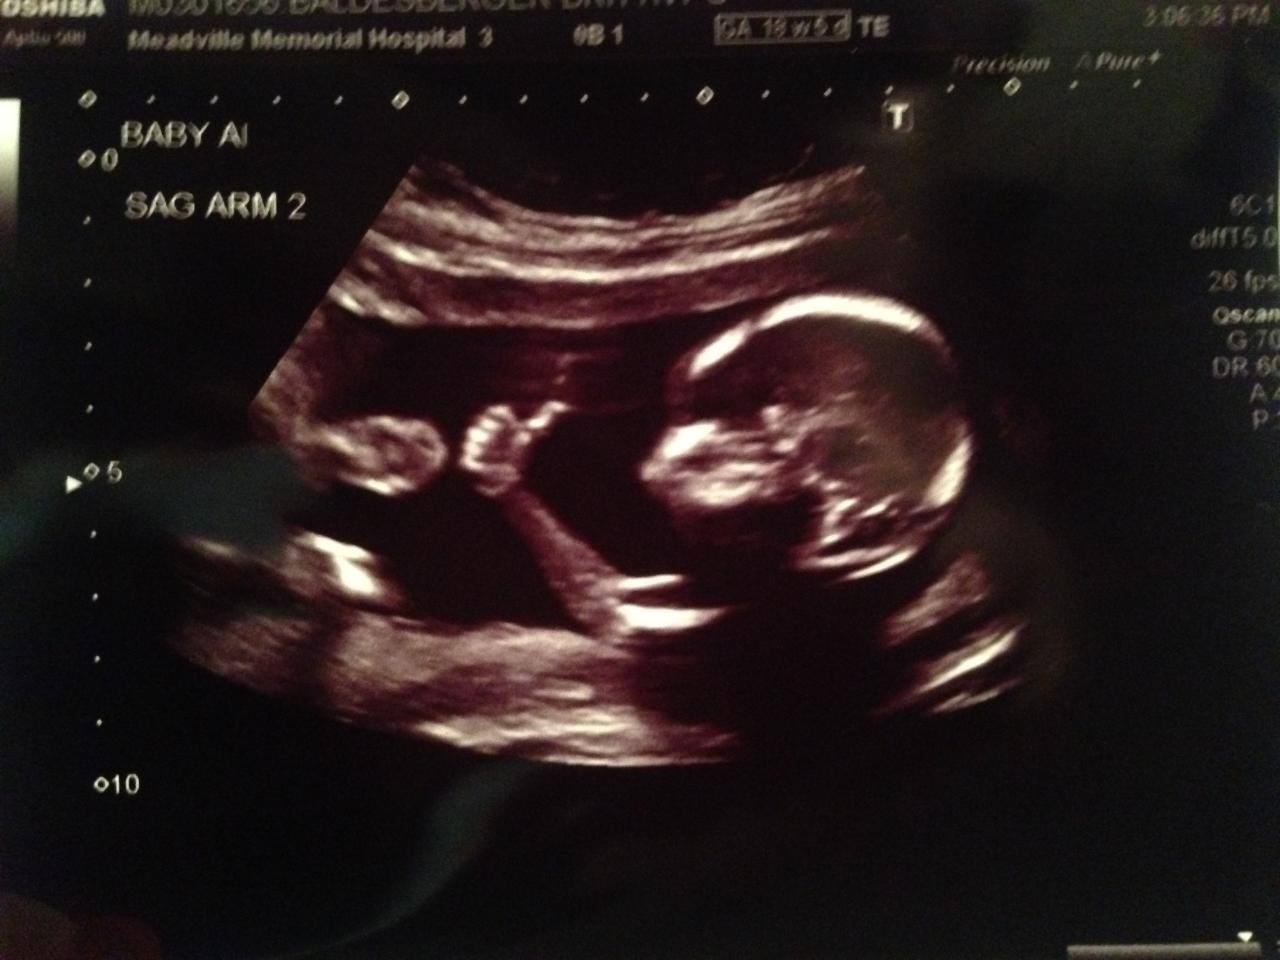

Futur père de famille, Brandon Hopkins a posté sur internet la photo de son bébé avec le pouce en l'air pendant l'échographie. Une posture qui fait le tour de la toile.

Avant même d'être né, ce bébé est déjà célèbre. Brandon Hopkins et sa femme attendent des jumeaux. Quelle ne fut pas leur surprise lorsqu'en pleine échographie, ils ont aperçu l'un des deux bébés avec le pouce en l'air. En rentrant, le futur papa a immédiatement posté l'image sur le site Reddit ."Les résultats de la dernière échographie semblent positifs" a-t-il ironisé en publiant la photo. Mais il ne se doutait pas que cette image aurait un succès mondial. En quelques jours, des millions d'internautes ont partagé le cliché sur la toile. "Mon frère m'a appelé pour me dire que mes bébés étaient célèbres", a-t-il déclaré à HLN-TV. Medisite aussi n'a pas pu résister à l'envie de partager cette photo insolite.

Cliquez pour agrandir l'image du foetus avec le pouce en l'air :